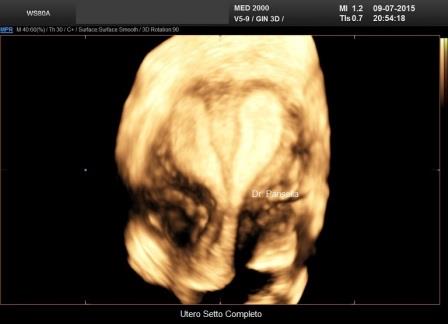

Utero Setto

E' la malformazione uterina più frequente (55% delle anomalie mulleriane); è la conseguenza di un incompleto riassorbimento del setto uterovaginale dopo la fusione dei dotti di Muller.

Ecograficamente è fondamentale la visualizzazione del profilo del fondo uterino per differenziarlo dall'utero bicorne. Nell'utero setto il profilo del fondo può essere convesso, appianato o a volte concavo. L'eco 3D, permettendo una accurata scansione coronale consente, nella maggior parte dei casi, di poter differenziare questa anomalia dall'utero bicorne.

Si distinguono due tipi di utero setto:

- utero setto completo: il setto si estende dal fondo alla cervice

- utero setto incompleto: il setto origina dal fondo e non giunge all'OUI.

L'utero setto è facilmente correggibile per via isteroscopica.